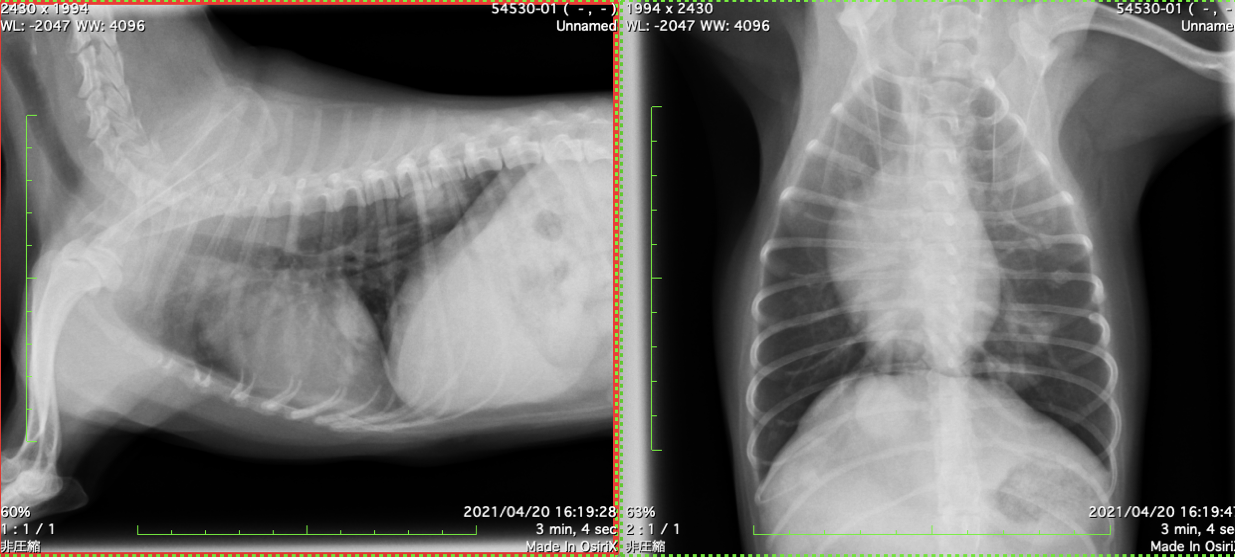

③ 胸部/腹部レントゲン検査 (図3 単純レントゲン画像:乳腺腫瘍の肺転移)

図3 単純レントゲン画像:乳腺腫瘍の肺転移